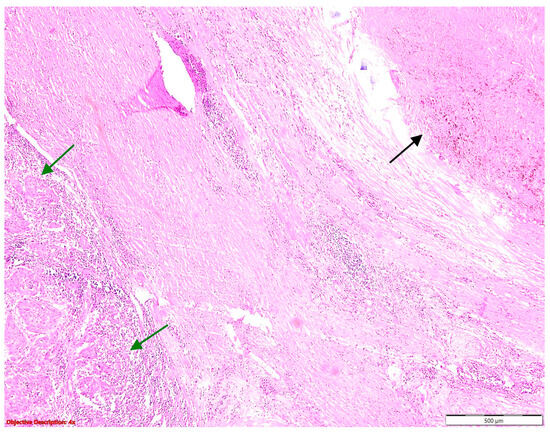

A histopathological examination of surgical resection specimens highlighted the presence of the following associations between NSCLC and other tumoral and nontumoral, and infectious and noninfectious pathological lesions, including nine cases of granulomatous inflammation, ten cases of fibronodular lesions, five cases of fibronecrotic nodules (Figure 1), two nodular calcifications, four instances of osseous/osteomedullary metaplasia, three cases of pneumoconiosis, two benign tumors, four lung infarctions, one instance of aspiration pneumonia, and one meningothelial-like nodule (Table 1).

Figure 1. Fibronecrotic nodule (left side) in the lung parenchyma (right side); HE, 40×.

Figure 4. Fibronodular lesion (left side) in the lung parenchyma (right side); HE, 40×.

Figure 10. Coexisting lesions: lung carcinoma () and fibronodular lesion (→); HE, 40×.